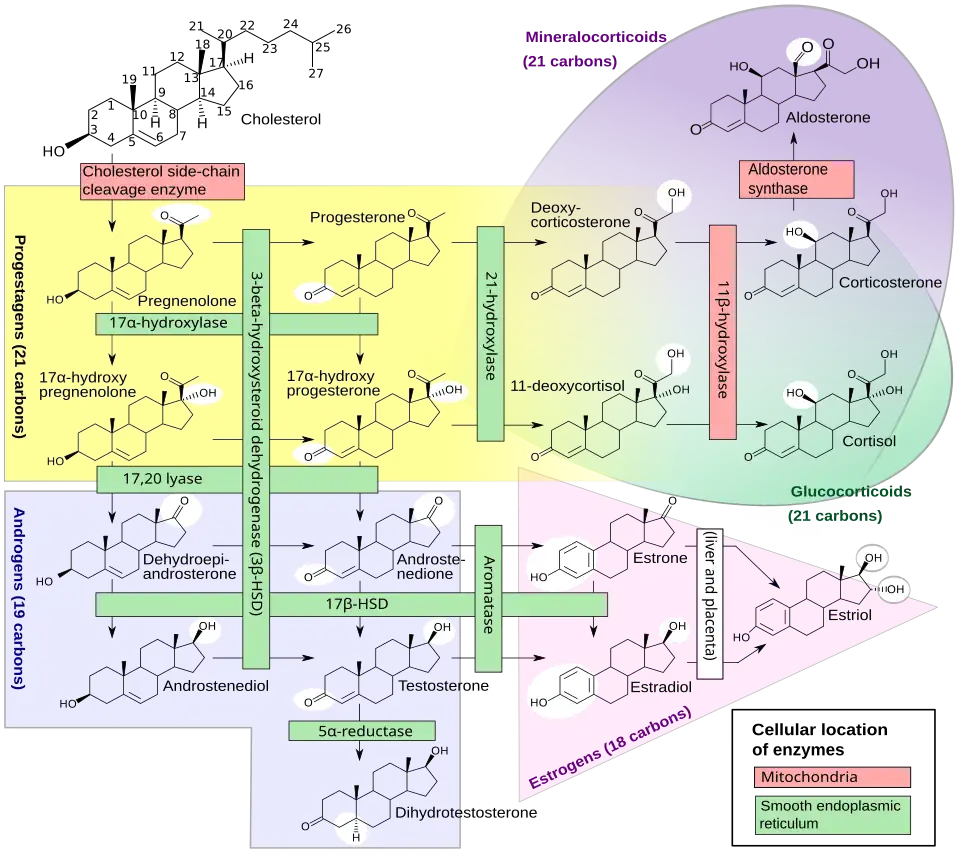

General images –